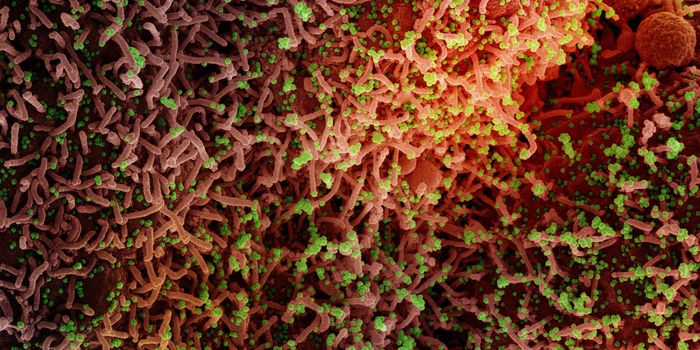

APR 29, 2020Clinical & Molecular DXThe coronavirus disease 2019 (COVID-19) is caused by severe acute respiratory syndrome coronavirus 2 (SARS-CoV-2). Incre ...

APR 01, 2020Clinical & Molecular DXResearchers have begun efficacy testing for a new SARS-CoV-2 diagnostic kit that claims to be able to test for COVID-19 ...